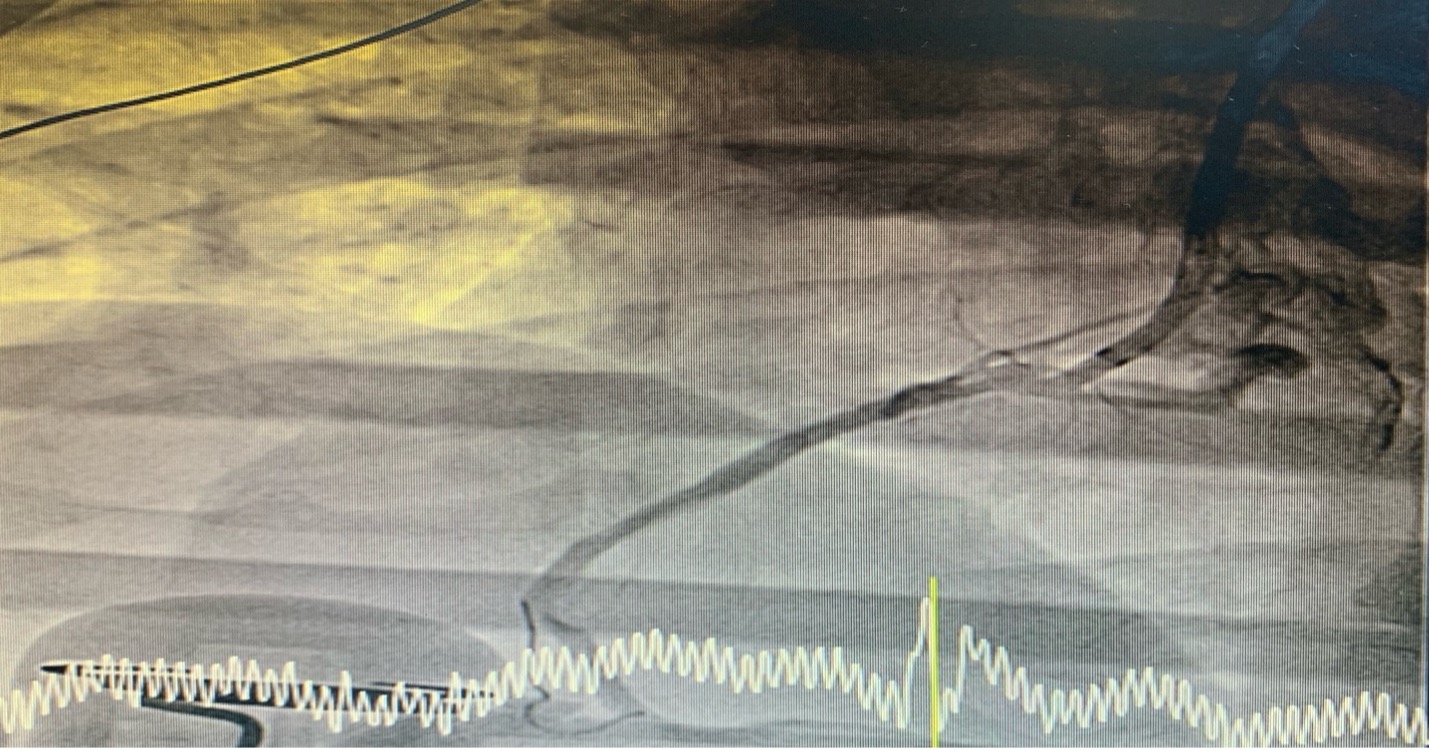

Coronary angiogram (CAG) via right femoral approach with JL 6/4 diagnostic catheter, JR 6/4 guiding catheter catheter showed normal Left main (LM), mild irregular, non significant stenosis left anterior descending artery LAD, LCx, complete blockage of proximal RCA.

CAG showed normal Left main, mild irregular, non significant stenosis left anterior descending artery, LCx , complete blockage of proximal RCA.

PCI with JR 6/4 guiding catheter and wiring with Turntrac to RCA. Predilated with 2.0 x 15 mm Semi-compliant balloon upto 14 atm. Biolimus eluting stent deployed proximal RCA upto 10 atm, Balloon stent post dilated upto 14 atm. The final angiogram was acceptable result. Inserted temporary pacemaker via right femoral vein. After arrived CCU the patient developed cardiac arrest c VT storm. Left Stellate ganglion block was done during CPR and successful suppression of VT storm .